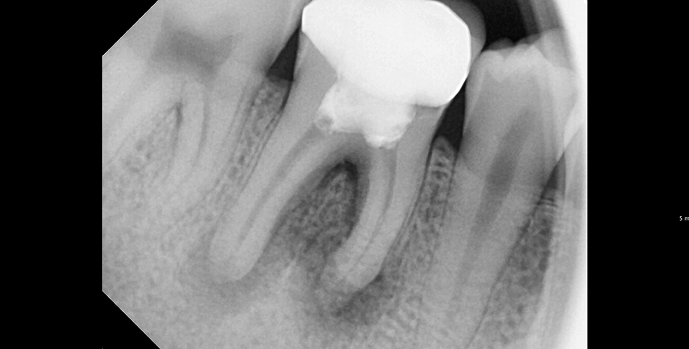

진단 및 영상검사

X-ray(필요 시 3D CT)로 염증 범위와 근관 형태를 확인하고, 통증 원인을 정밀 평가합니다.

BEFORE & AFTER

• 20대 남성 | 치근단병소 | 재신경치료 | 치료기간 4주

Before 2025.04.30

After 2025.05.29